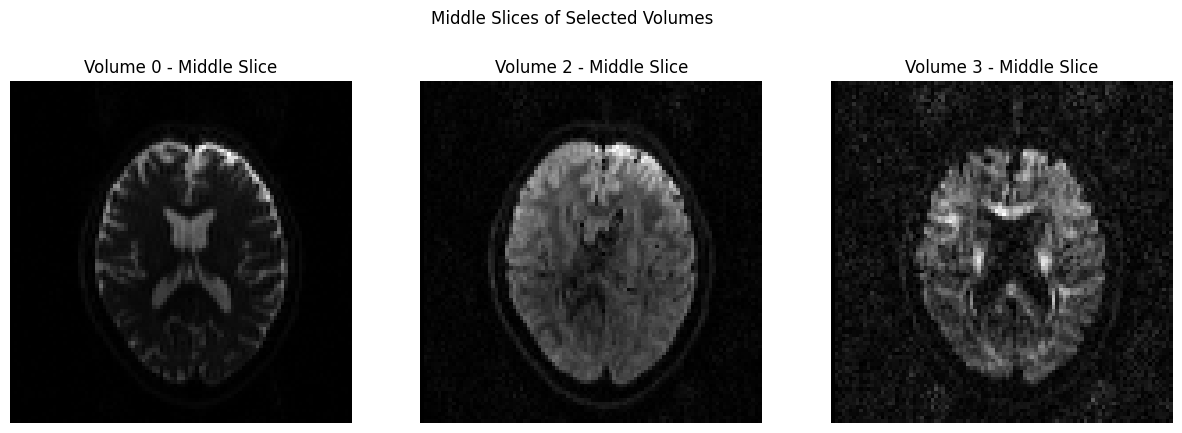

Visualization#

In order to view the image, we will use a couple of different packages, and you can determine which one you prefer. The first one we will use it matplotlib, which was loaded earlier in this notebook. In the code below, we will temporarily convert the data to NIFTI format and plot 3 volumes with Matplotlib.

dwi_file = 'sub-CON02_ses-preop_acq-AP_dwi.nii.gz'

# Load the NIfTI file

nii_image = nib.load(dwi_file)

data = nii_image.get_fdata()

# Define volume indices for the three volumes you want to display

volume_indices = [0, 2, 3]

slice_index = data.shape[2] // 2 # Choose the middle slice for visualization

fig, axes = plt.subplots(1, 3, figsize=(15, 5))

for i, vol_idx in enumerate(volume_indices):

# Extract the middle slice from the selected volume and rotate it 90°

rotated_slice = np.rot90(data[:, :, slice_index, vol_idx])

axes[i].imshow(rotated_slice, cmap="gray")

axes[i].set_title(f"Volume {vol_idx} - Middle Slice")

axes[i].axis("off")

plt.suptitle("Middle Slices of Selected Volumes")

plt.show()